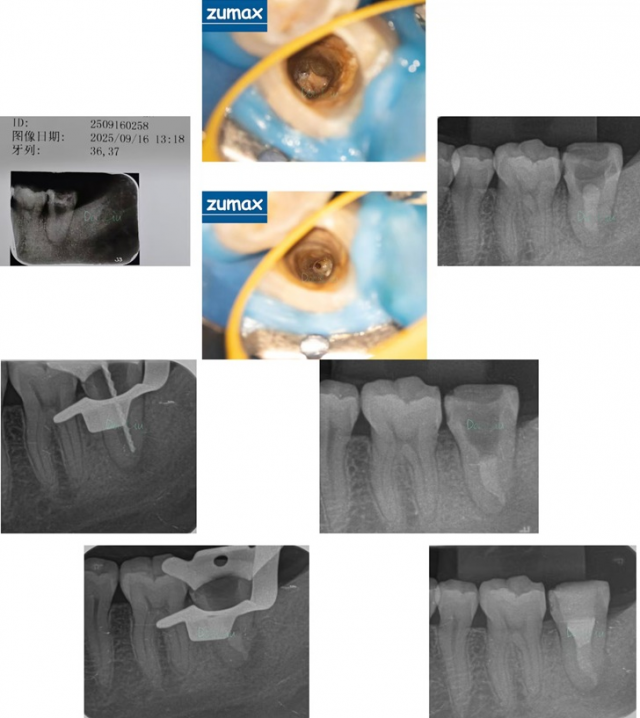

【病例展示

病例二

病例二.jpg

病例三

微信图片_20251229170033_129_45.jpg

【现场精彩】